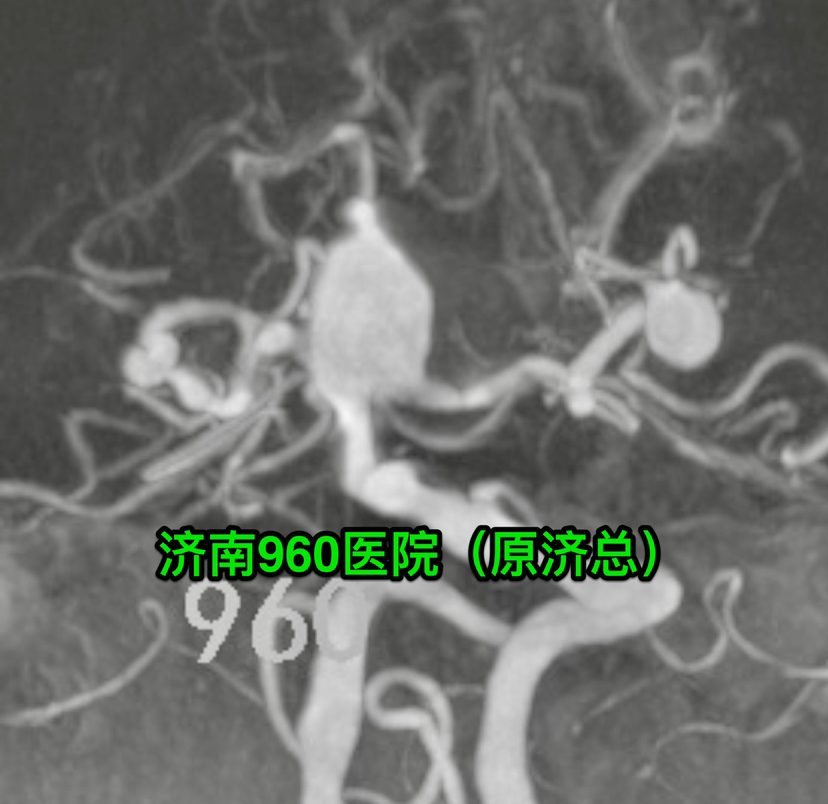

DSA检查发现颅内共12枚形态各异的动脉瘤,其中基底动脉瘤形态不规则,大小约15*13mm,瘤颈部累及双侧大脑后动脉P1段,双侧后交通动脉和前交通动脉不显示,瘤顶部有子囊发出。

尽管患者多发动脉瘤,结合DSA显示基底动脉顶端大型动脉瘤,瘤顶部有子囊发出,磁共振显示动脉瘤顶部突入三脑室,CT显示蛛网膜下腔出血主要在三脑室、四脑室和小脑表面,判定基底动脉顶端动脉瘤是本次出血的责任动脉瘤。考虑介入治疗可能需要双支架置入,术后抗血小板治疗增加其它动脉瘤破裂出血风险,遂决定对患者进行经鼻蝶入路切除复发垂体瘤并对基底动脉顶端动脉瘤进行夹闭。